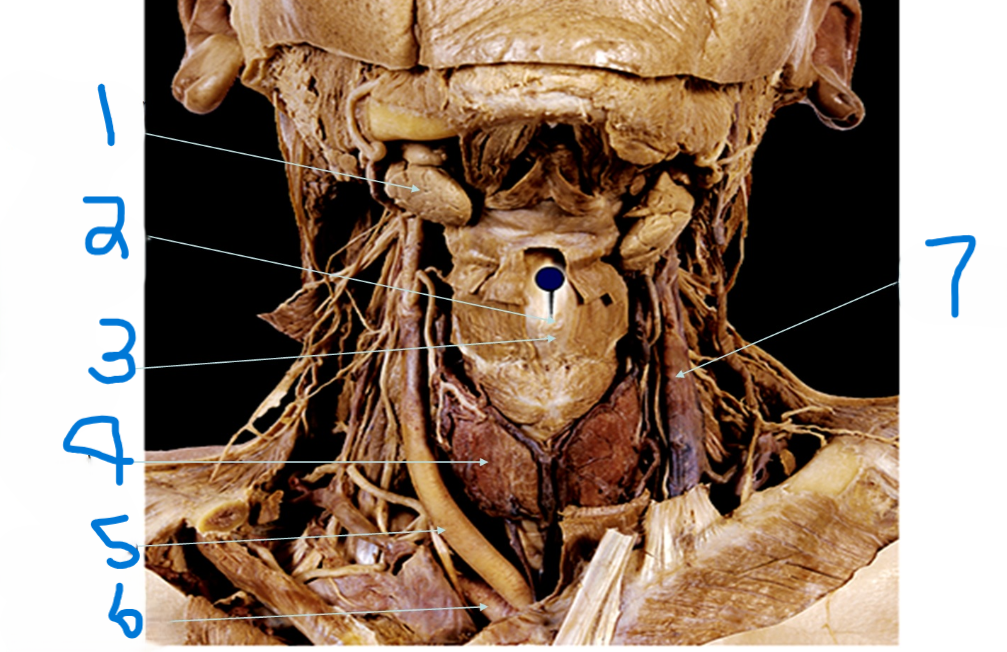

What is depicted by #1

Laryngeal Prominence (adams apple)

What is depicted by #2

Thyroid cartilage

What is depicted by #3

Thyroid gland

What is depicted by #4

Right common carotid artery

What is depicted by #5

Right subclavia artery

What is depicted by #6

Left internal jugular vein

What is depicted by #7